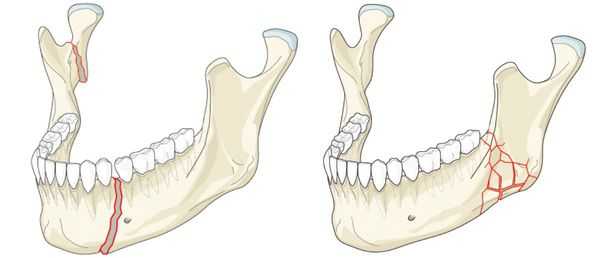

Переломы нижней челюсти возникают в месте приложения травмирующей силы (прямые) и вследствие перегиба (отраженные). Чаще бывают переломы в области клыков, резцов, углов и шеек, реже - венечного отростка. Бывают одиночные, двойные и множественные переломы. Переломы нижней челюсти отличаются разнообразием смещения отломков, что связано с действием мышечной тяги; при переломе тела челюсти смещение выражено резче при расположении линии перелома ближе к углу, чем к подбородку. Переломы в области зубного ряда, как правило, открытые.

Что касается локализации переломов, наиболее частой областью перелома является угол нижней челюсти; затем следуют переломы мыщелковых отростков, коренных зубов и подбородочного отдела. Срединные переломы встречаются реже, что объясняется толщиной челюсти в этой области.

Переломы в области угла и тела нижней челюсти

Неблагоприятные переломы угла нижней челюсти обычно происходят вследствие разрыва собственно жевательной и внутренней крыловидной мышц со смещением проксимального сегмента кверху. Это лучше всего определяется при рентгенографии.